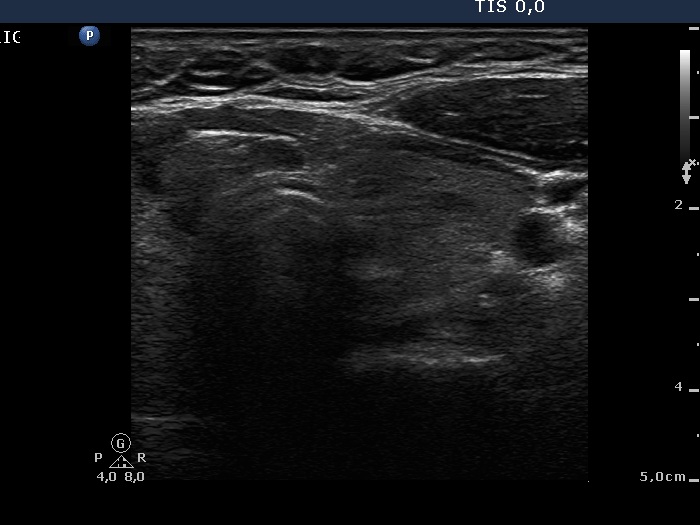

The role of complex diagnosis - follicular proliferation - Case 2. (ultrasonographic picture 6)

Right lobe, longitudinal scan